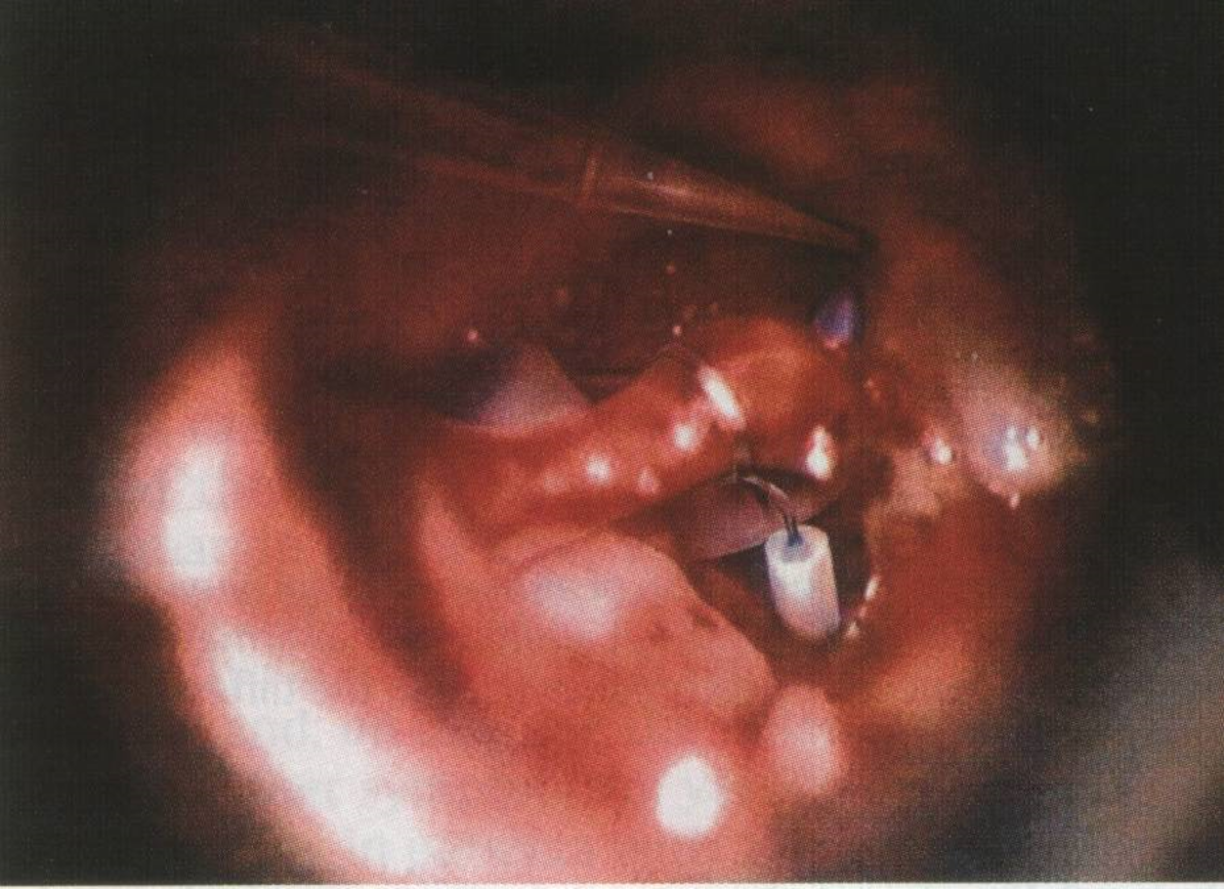

- Surgery: Stapedectomy

Stapedectomy operation: